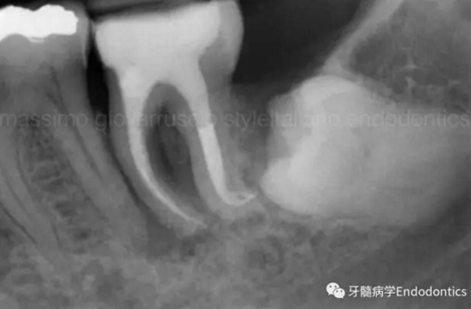

圖6.術(shù)后X線片顯示在根管機(jī)械預(yù)備后保留了原始的根管解剖形態(tài)結(jié)構(gòu)。冠方預(yù)敞和探查保證了對(duì)整個(gè)根管解剖形態(tài)結(jié)構(gòu)的保護(hù)。

圖7.具有解剖障礙的根管,比如根尖區(qū)不規(guī)則的直根管、存在不規(guī)則急彎的彎曲根管。

圖8.這個(gè)根管需要智慧和毅力才能越過。難點(diǎn)在于通過在觸覺(通過手用器械傳來的感覺)感受到銼在根尖的阻力。這會(huì)發(fā)生是因?yàn)殇S的尖部會(huì)被不規(guī)則解剖形態(tài)干擾,而不是銼到全長(zhǎng)并超出。